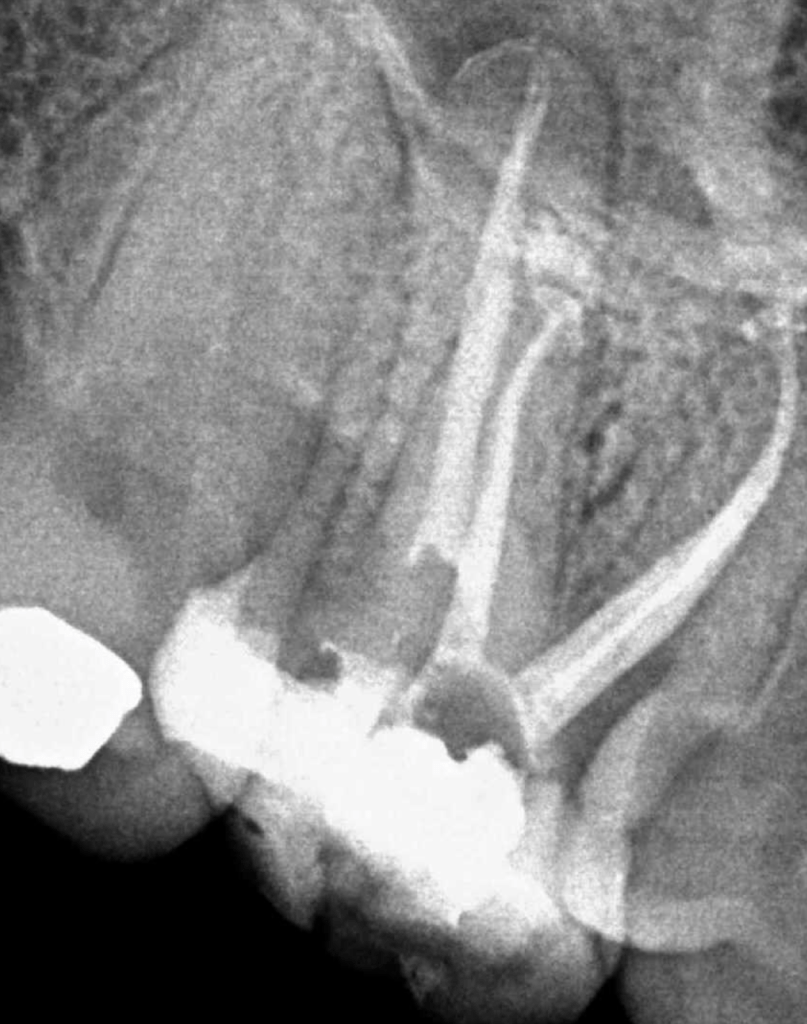

Vertical root fracture